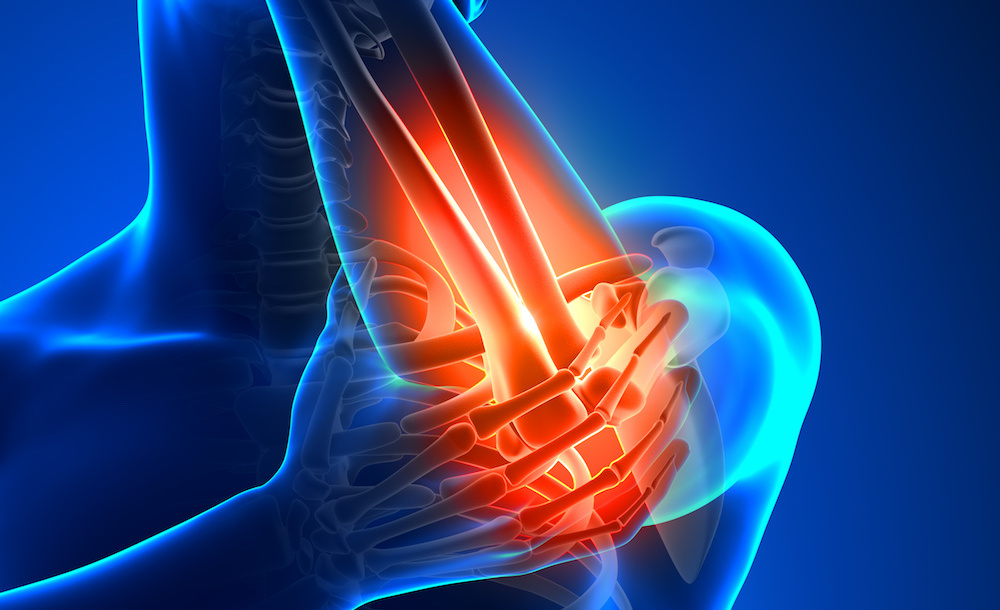

Peste 1,5 miliarde de oameni din lume suferă de dureri cronice, o problemă globală cu consecinţe severe asupra calităţii vieţii şi a economiei. Medicamentele opioide, deşi eficiente în controlul durerii, îşi pierd eficacitatea în timp, crescând riscul creşterii dozelor şi al dependenţei.